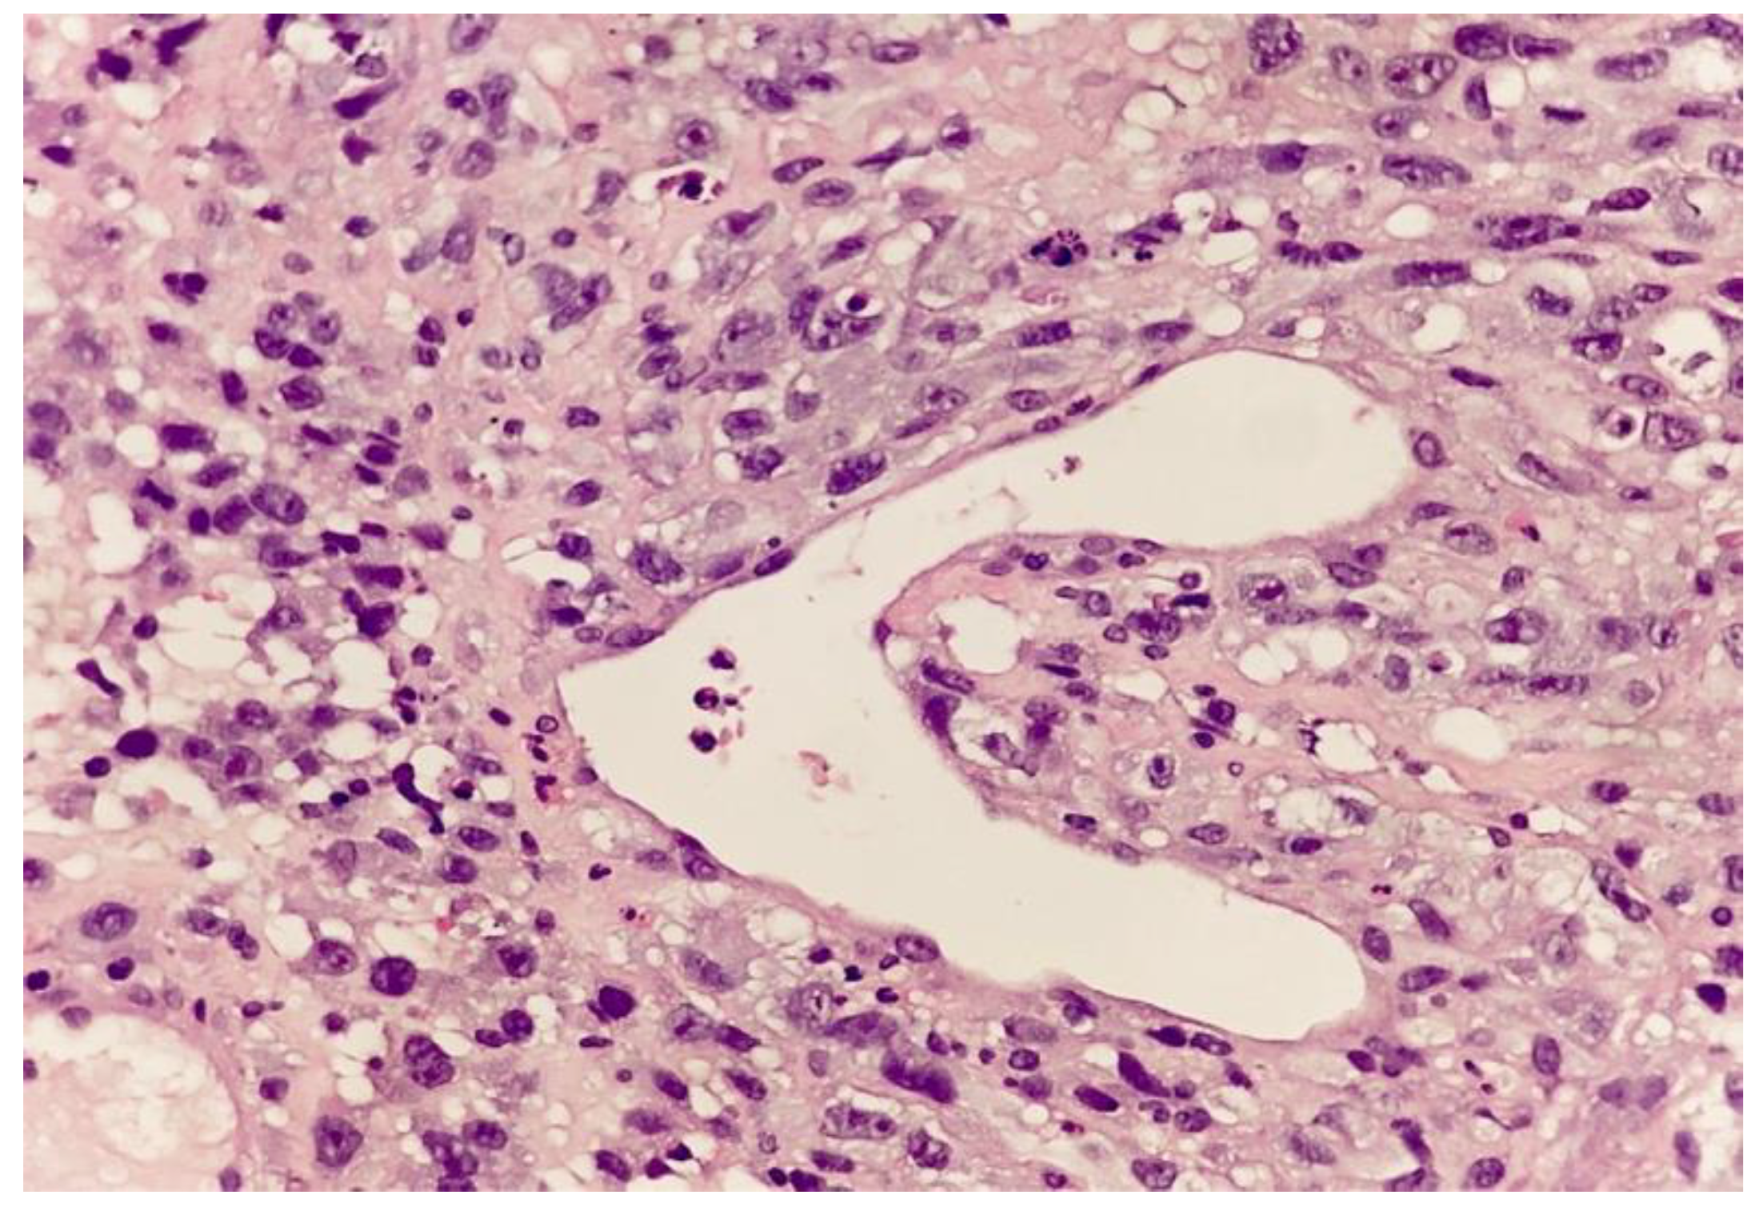

2. Case Report and Evolution